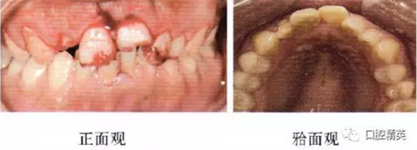

患者口腔衛(wèi)生狀況差,開始牙周基礎(chǔ)治療。治療前牙周檢查記錄見圖5,治療后牙齦色形質(zhì)有明顯改善(圖6),前牙區(qū)齦緣仍略有水腫,囑注意口腔衛(wèi)生。1周后行2牙冠延長術(shù)(術(shù)前圖7),拆線后見清晰暴露斗的齦下邊緣(圖8)。囑8周牙齦位置穩(wěn)定后行最終修復(fù)。

圖7 2冠延長術(shù)前口內(nèi)像

圖8 2冠延長術(shù)后拆線即刻口內(nèi)像